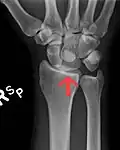

The lunate bone is the most frequently dislocated carpal bone.

Dislocated lunate -